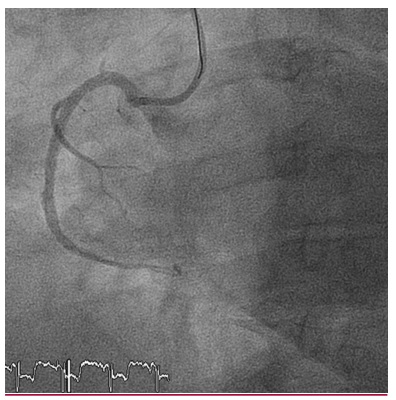

Manejo controvertido de trombocitopenia grave inducida por abciximab